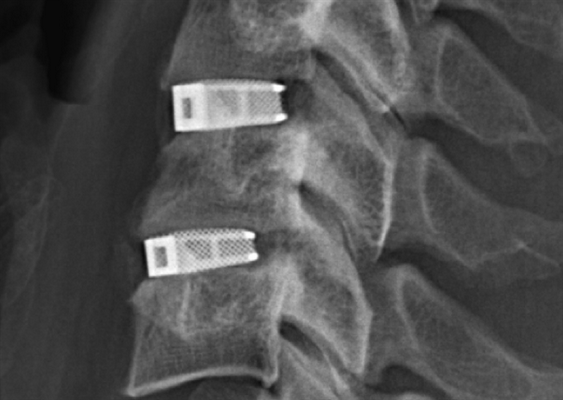

Сформированный спондилодез на уровне L3-L4.